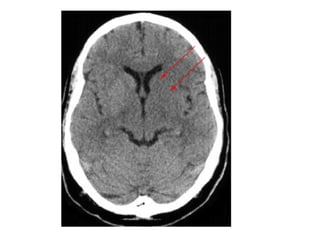

NECT shows hyperdense internal veins and bilateral (R > L) thalami

hypodensities , compatible with dural vein thrombosis and venous